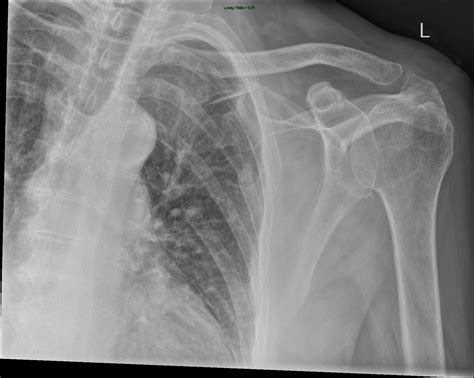

The shoulder is a complex joint involving multiple bones, ligaments, and tendons. To classify a scan as a Normal Shoulder Xray, a radiologist must observe clear, distinct features that indicate the absence of fractures, dislocations, or degenerative bone diseases. The shoulder is primarily a ball-and-socket joint, technically known as the glenohumeral joint.

On a standard radiograph, the primary structures evaluated include:

• The Humerus: Specifically the humeral head, which is the “ball” of the joint. It should appear smooth and rounded.

• The Glenoid: The “socket” part of the scapula (shoulder blade). In a healthy scan, the space between the humeral head and the glenoid should be uniform.

• The Acromion and Coracoid Processes: Bony projections of the scapula that serve as anchor points for ligaments and muscles.

• The Clavicle: The collarbone, which connects to the acromion at the acromioclavicular (AC) joint.

Even with advanced technology like MRIs and CT scans available, the Normal Shoulder Xray is rarely skipped. It serves as a rapid, cost-effective, and highly accessible way to screen for major structural abnormalities. It is the preferred method for identifying:

• Acute Fractures: If you have fallen on your shoulder, an X-ray can immediately confirm if the humerus, clavicle, or scapula is broken.

• Dislocations: It quickly confirms if the humeral head has slipped out of the glenoid socket.

• Osteoarthritis: By looking for the narrowing of the joint space or bone spurs (osteophytes), doctors can diagnose wear-and-tear conditions.

• Calcific Tendonitis: Sometimes, calcium deposits can build up in the tendons, which show up as white, cloudy spots on an otherwise clear X-ray.